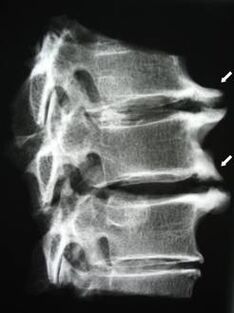

Im Anfangsstadium wird Osteochondrose mittels MRT erkannt.. Anschließend kann die Pathologie durch Röntgen diagnostiziert werden. Auf Röntgenaufnahmen der Halswirbelsäule werden eine Verringerung des Wirbelabstands, pathologische Veränderungen der Facettengelenke und Osteophytose festgestellt.

| Zervikale Osteochondrose | Das Auftreten pathologischer Veränderungen in einem oder mehreren Bewegungssegmenten der Wirbelsäule. Beeinträchtigung der Beweglichkeit der Wirbelsäule, Entwicklung myofaszialer Schmerzsyndrome und Einklemmen der Wirbelsäulenwurzeln. | Schmerzen, Parästhesien und motorische Veränderungen im Halsbereich, die sich bis zum Hals und den oberen Extremitäten erstrecken. Erkennung charakteristischer Veränderungen der Wirbelsäule mittels MRT und Röntgen (Osteophyten, verringerter Wirbelabstand, Anzeichen einer Schädigung der Zwischenwirbelgelenke) |